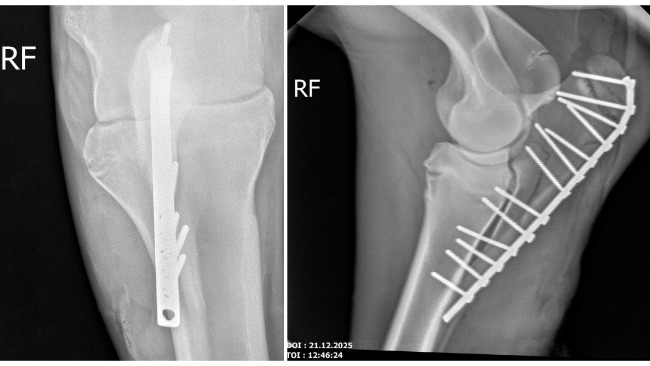

Dzięki Waszej pomocy operacja Zuzi zakończyła się sukcesem. Klacz bezpiecznie opuściła klinikę i obecnie przebywa w pensjonacie dla koni, gdzie jest pod stałą opieką i spokojnie dochodzi do siebie po zabiegu.

Do połowy lutego Zuzia musi mieć ściśle ograniczony ruch — pozostaje zamknięta w boksie, aby kość mogła się prawidłowo zrosnąć. Po tym czasie zaplanowana jest kontrola lekarska. Jeśli badania potwierdzą, że wszystko goi się prawidłowo, Zuzia zacznie bardzo ostrożne wdrażanie do stępa.